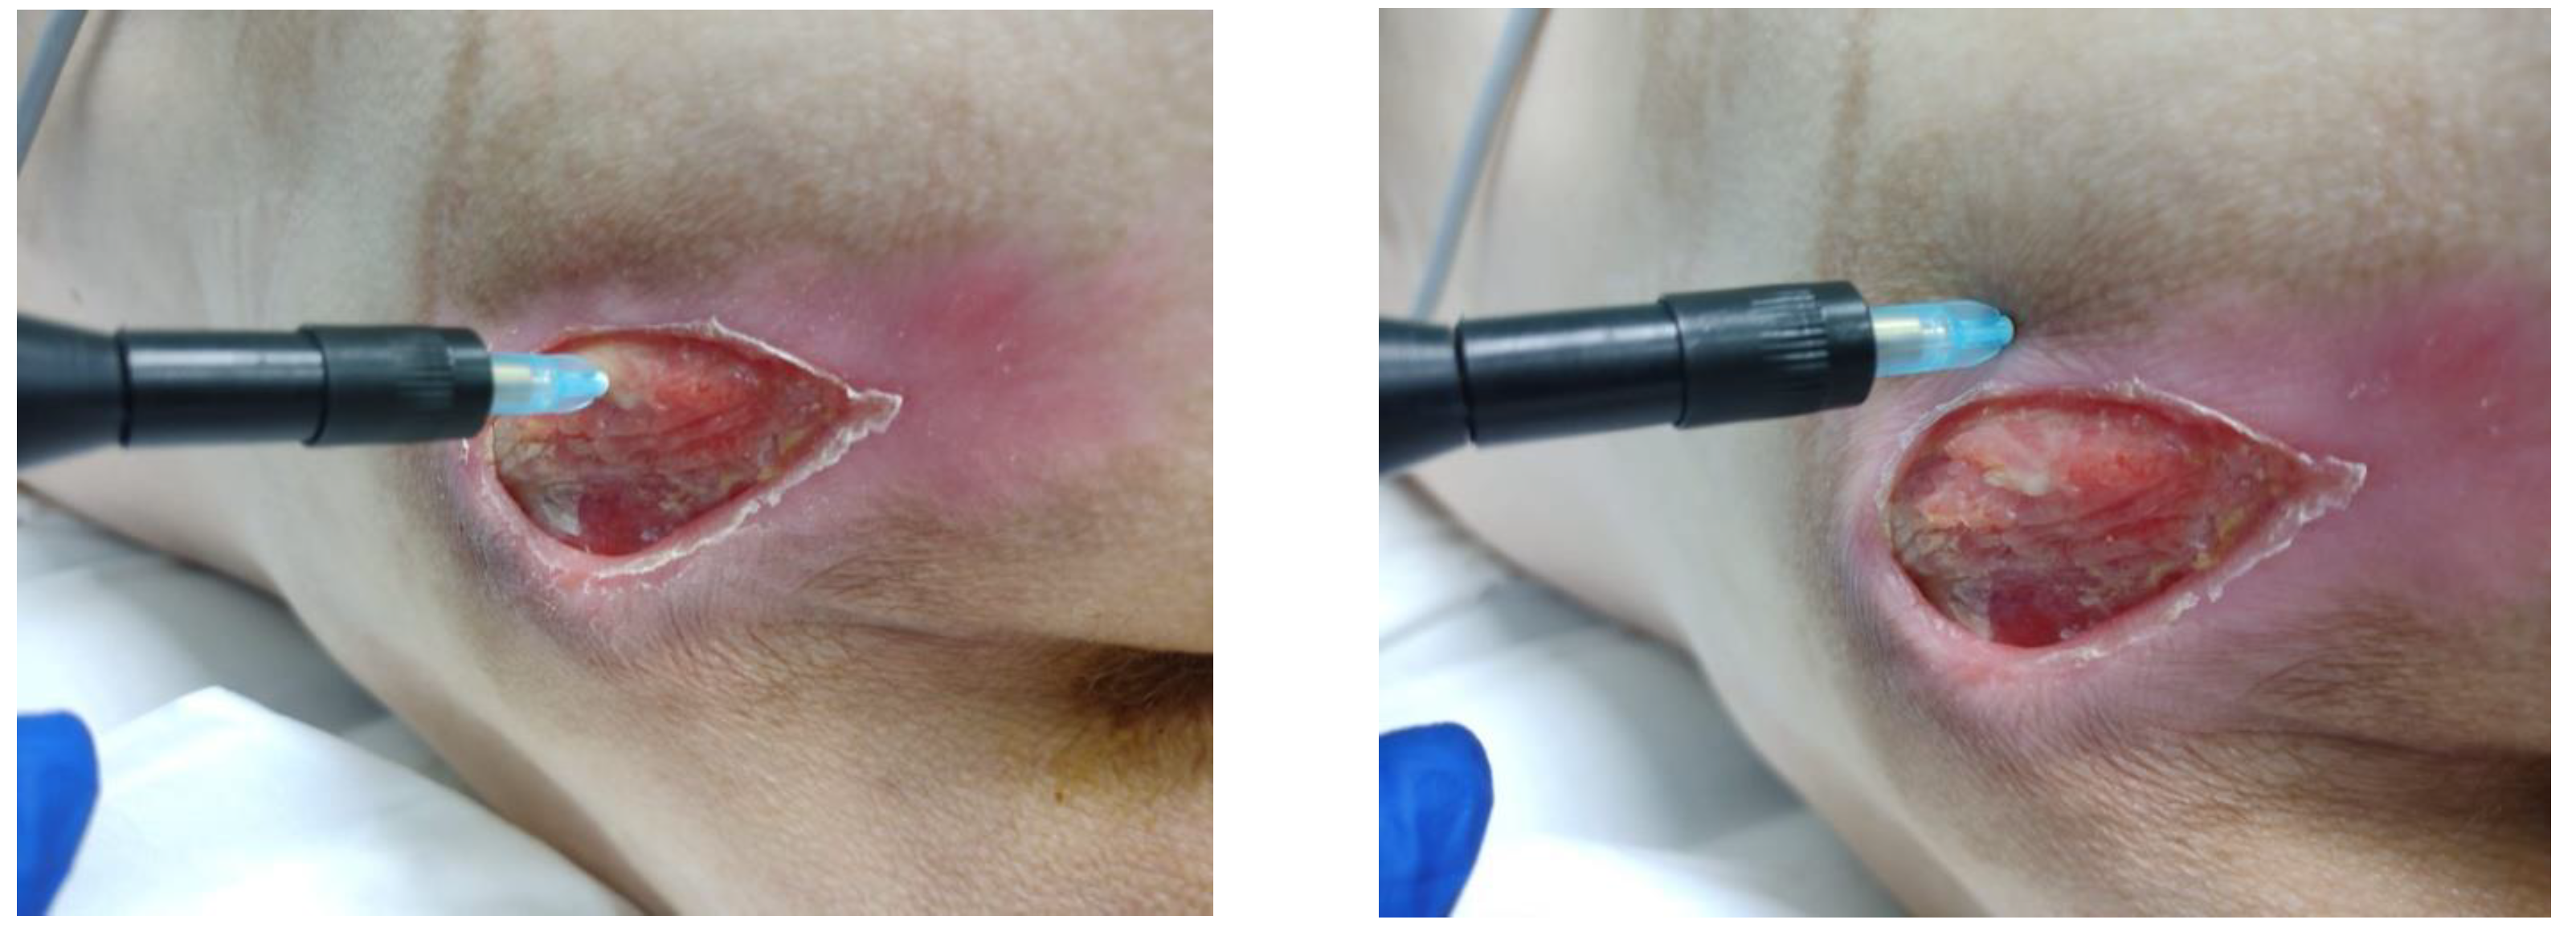

3.2. Clinical Research

3.3. Morphological Studies